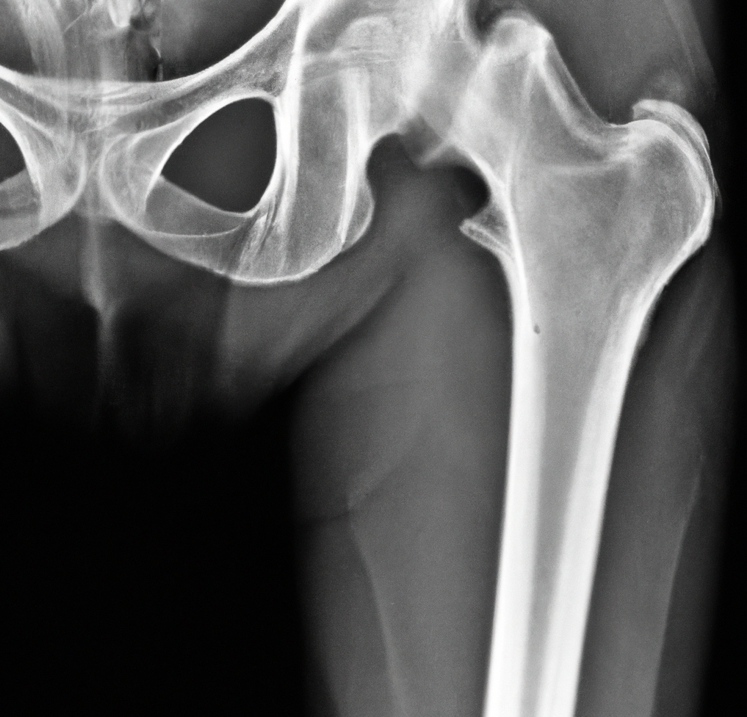

골다공증에 도움 되는 운동요법

골다공증을 예방하고 관리하기 위해 규칙적이고 몸에 맞는 적절한 운동요법이 매우 중요합니다. 다음은 골다공증에 도움 되는 운동 요법 몇 가지입니다.